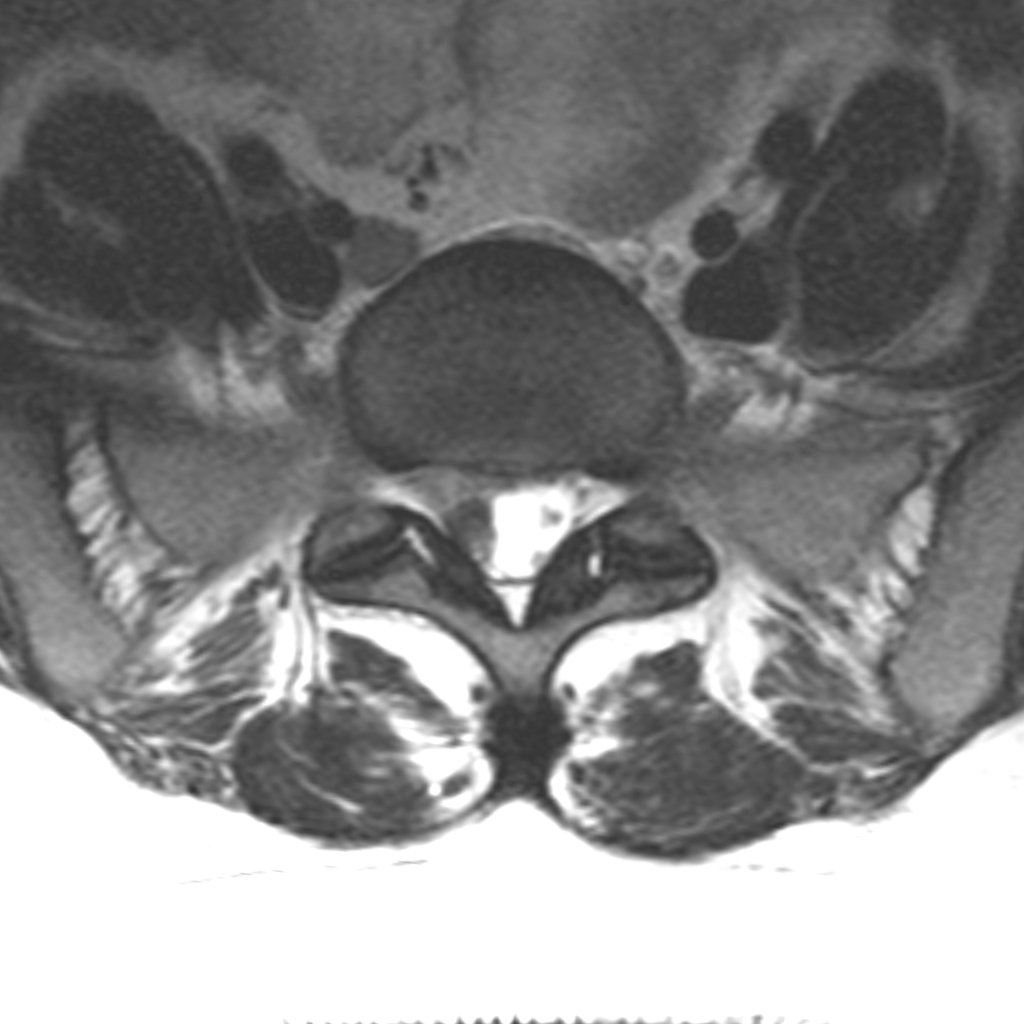

Axiális MRI felvétel — műtét utáni állapot

MRI: post-operative status — nerve root decompressed

The procedure involves exposing the spine through a small incision (2–3 cm) and creating a minimal bony window between two vertebrae. Through this, the herniation compressing the nerve is removed and the neural elements are decompressed.

There is no clinically significant difference between currently available methods — conventional, microdiscectomy, and endoscopic discectomy. Whenever possible, I favour the minimally invasive approach.